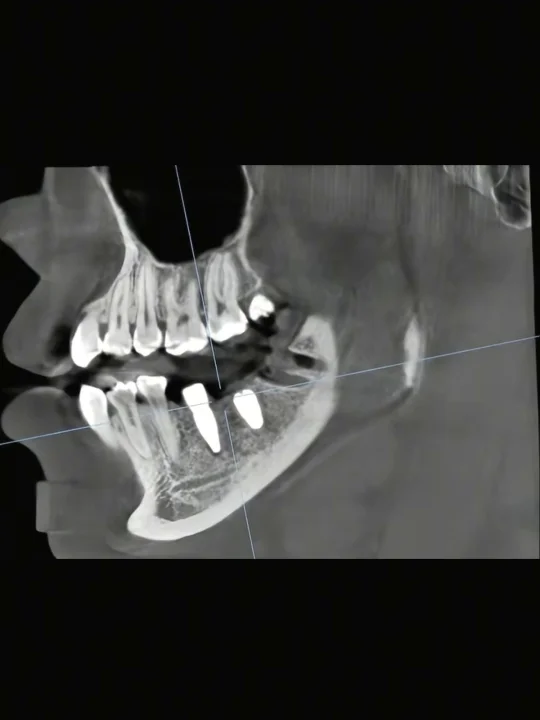

去年年底到今年年初,左下最里面两颗大牙都疼,前几天还不严重,后面睡觉直接疼醒,趁着假期去看,智齿得拔,旁边的大牙也得拔,牙根被顶坏了。。。一次拔两颗大牙 一颗智齿[再见R]还得多种一颗牙[再见R]没办法,不管的话后面牙齿只会越来越差:( 现在6号牙已经做完二期7号牙还得等一个月,张晓欣最初说的是可以一起种两颗,也可以分开,间隔一个月没啥问题,想着前几个月拔牙脸肿,就分开的,种完左边脸比较肿,可是比之前好多了,冰敷一两天就消肿不少。两颗种的都是iti植体,自费13张,还好没植骨啥的,不然要肿成🐷头,两期都是他给我种的,一个月后弄另一颗的二期,到时候再一起弄冠。

种植牙看牙武汉种牙爱合种牙日记